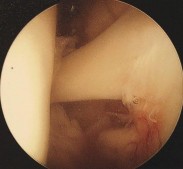

Question 12:

Following a primary total knee arthroplasty, a patient experiences isolated patellar clunk syndrome. Which of the following implant designs or technical factors is most closely associated with this phenomenon?

Correct Answer: Posterior-stabilized (PS) femoral component with a high intercondylar box

Explanation:

Patellar clunk syndrome occurs in posterior-stabilized TKA when a fibrotic nodule forms at the superior pole of the patella. During extension, this nodule catches in the intercondylar box of the femoral component and "clunks" out as the knee reaches full extension.